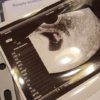

@Katy83 piękna fasolka!! :)